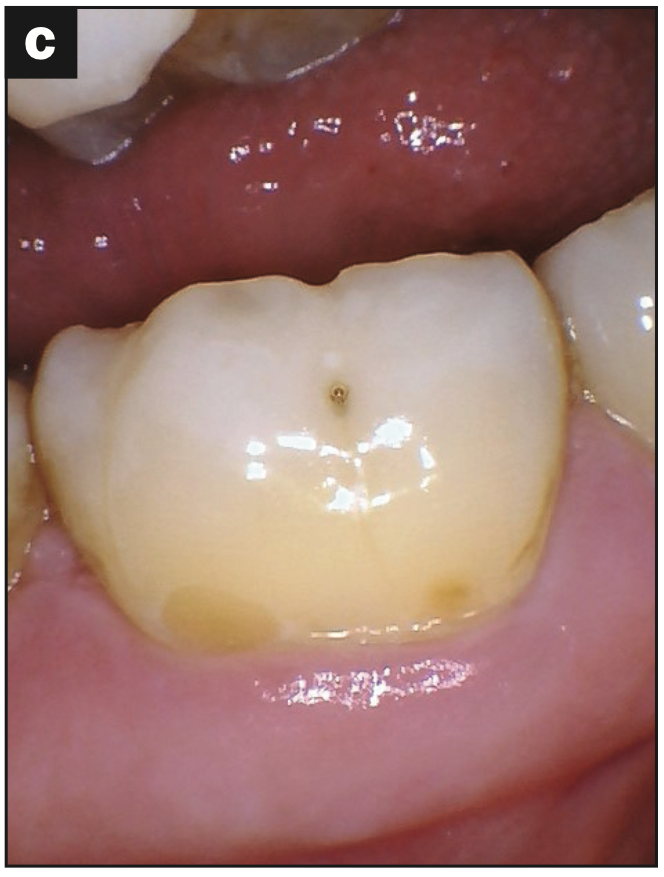

- Abfraction with decay (Figures 2a and 2b)

- Abfraction lesions (Figures 2c and 2d)